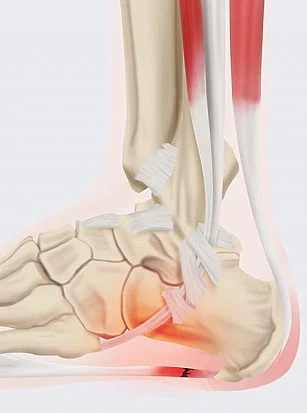

족저근막염은 쉽게 말해 발바닥 근육을 덮고 있는 막에 생긴 염증을 의미합니다. 족저근막은 발뒤꿈치뼈부터 발끝까지 이어지는 두껍고 강한 섬유로 발의 아치를 지탱해 발밑에 전달해지는 충격을 흡수하고 보행 시 발의 기둥이 되는 부분입니다.

이런 족저근막에 반복적인 미세 손상이 발생하게 되면 근막을 조직하는 콜라겐의 변성이 발생하며 이로 말미암아 염증과 진통을 보이는 질환을 족저근막염이라고 합니다.